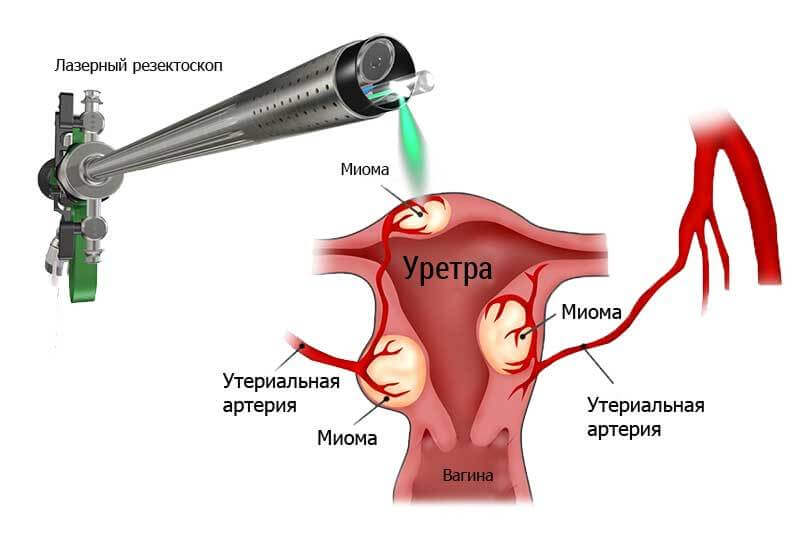

Современные методы лапаротомии и миомэктомии